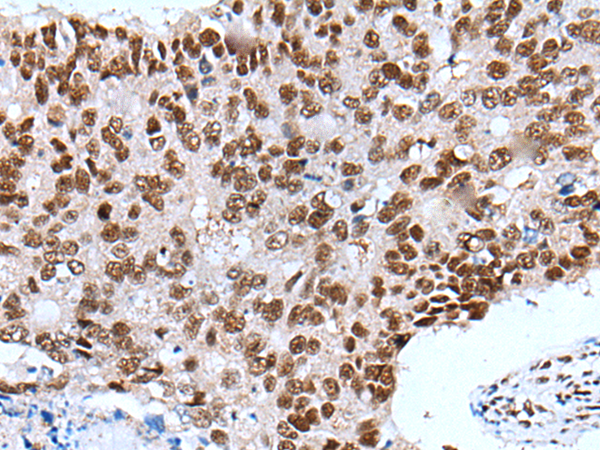

分类: 科研抗体货号: P05886别名: IL6Q; gp80; CD126; IL6RA; IL6RQ; IL-6RA; IL-6R-1应用: IHC反应种属: Human